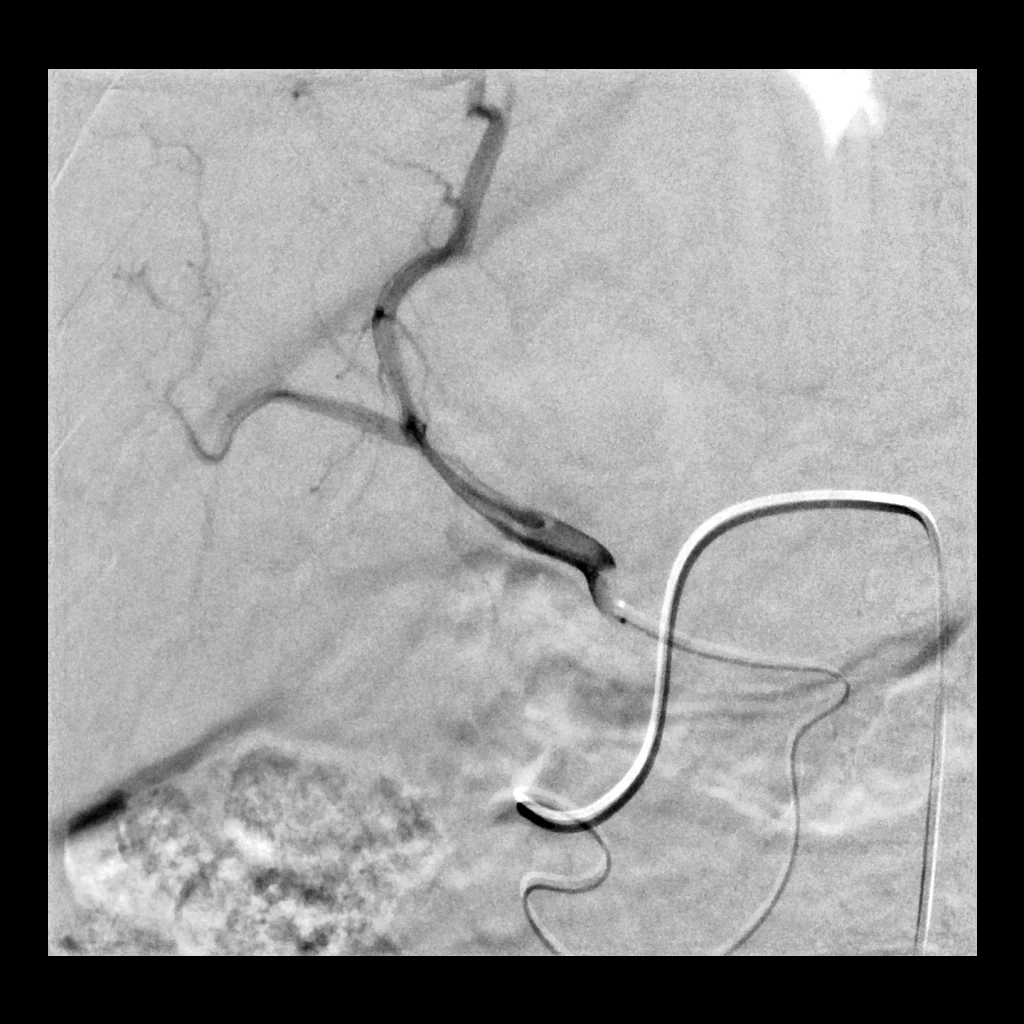

73 year old male with HCC and a known occlusion of the superior mesenteric artery. He presents for radioembolization.